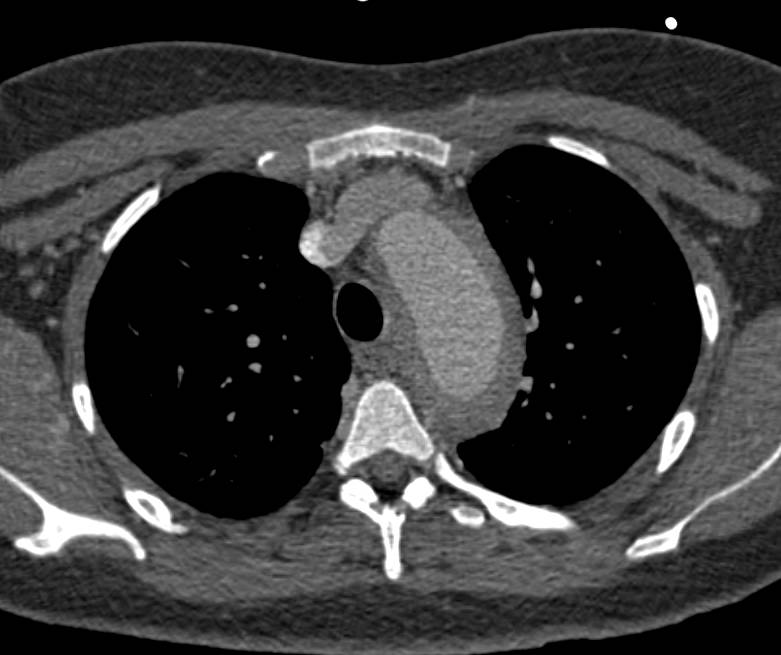

Thoracic Outlet Obstruction Symptoms with Kinked Left Subclavian Artery in 2 Positions